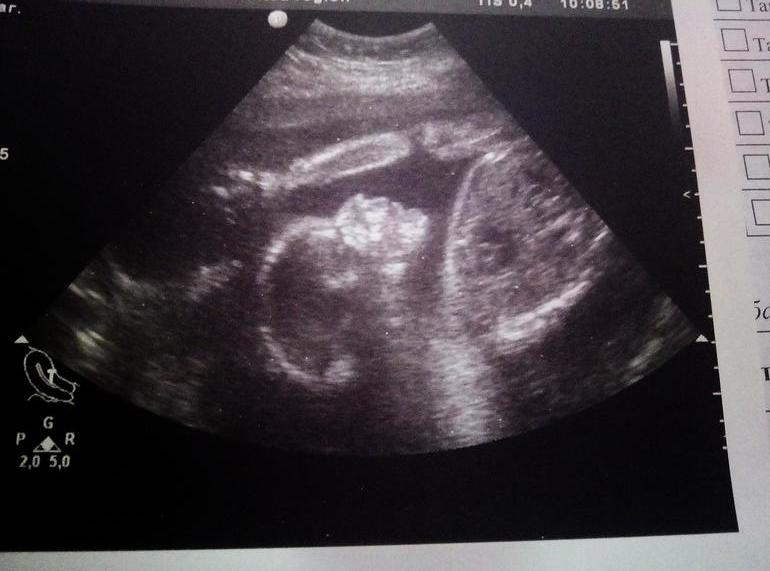

у нас мальчик😍

была сегодня на УЗИ, сказали 100% мальчик,муж сказал"Роберт"

В голове не укладывается...у меня сыночек))